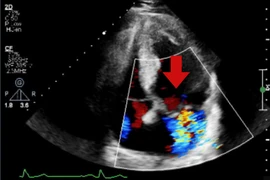

Vừa qua, Bệnh viện Việt Nam – Thụy Điển Uông Bí đã tiếp nhận và xử trí thành công một trường hợp người bệnh nữ 35 tuổi nhập viện do que cấy tránh thai “đi lạc” trong cơ bắp tay.

Người bệnh là C.T.L. 35 tuổi (Hải Dương) cho biết đã thực hiện cấy que tránh thai tại một phòng khám tư cách đây khoảng 4 tháng.